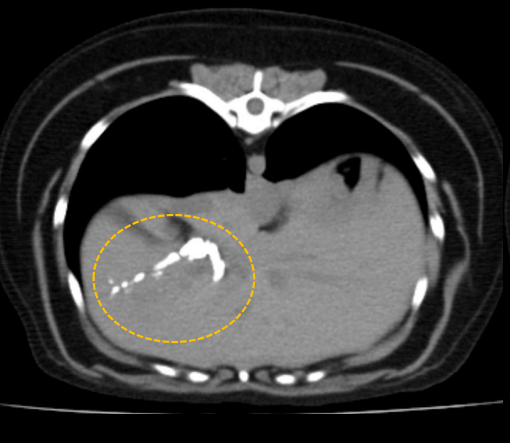

보다 정확한 위치, 분포등을 확인하기 위해서 CT 촬영을 실시했습니다.

출처 : 경기동물영상센터 CT소견 CT검사에서 간 우측 내측엽 담도 내 다량의 결석이 확인되었습니다.